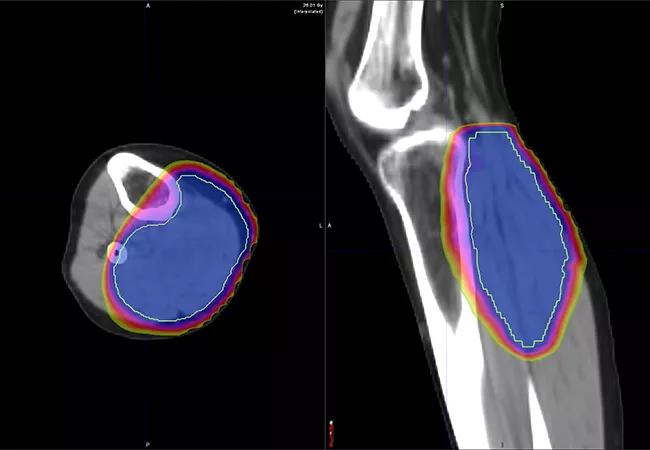

A new approach is reducing the wait. Instead of five to six weeks of radiation therapy, patients now have the option to undergo five days of hypofractionated external beam radiation. This shorter although higher daily intensity approach has been used in breast, lung and colorectal cancers. Cleveland Clinic is helping lead the charge in the sarcoma space.

Conventional neoadjuvant radiation therapy regimens consist of 50 Gy in 25 fractions delivered over the course of five weeks.

Short-course radiation therapy has been used for Cleveland Clinic patients with extremity sarcomas for about four years, according to Dr. Mesko. Patients receive five fractions over the course of five days. Surgery occurs 24 to 72 hours after the last dose of radiation.

Early outcomes reported by Dr. Mesko and colleagues suggest favorable local control and wound healing. In one study published in Advances in Radiation Oncology, 16 patients were treated for sarcomas in their lower extremity, upper extremity or trunk. Most were treated with 30 Gy in five fractions over five consecutive days, followed by resection. The median time to resection following the completion of radiation therapy was one day, and median time from initial biopsy results to the completion of primary oncologic therapy was 20 days.